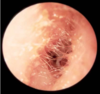

which ear is this otoscopic view?

This is the right ear drum as the light reflex and head of malleus is on the right